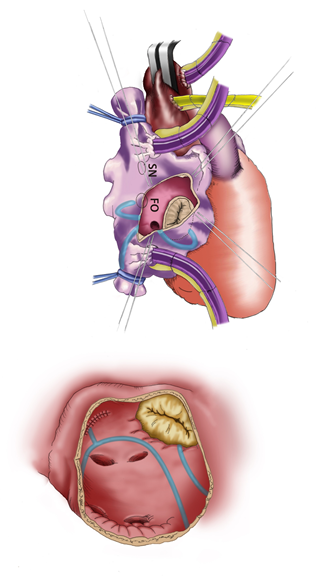

当院では、1992年から心房細動を手術で治療する「メイズ手術」を積極的に行っております。同手術は、不整脈の原因となる電気の流れを冷凍凝固により断ち切り(図1:水色線)、正しい電気の流れのみを残す手術になります。これまで合計1,100例を超える患者さんに行い、手術後1年で約92%の方が正しい脈に回復されています。